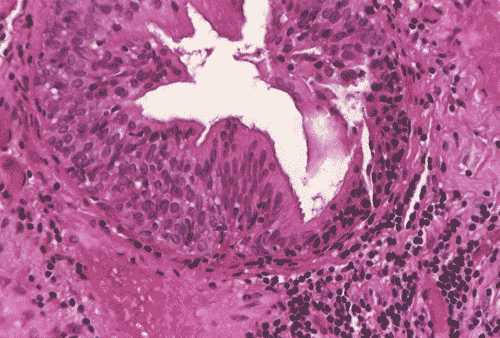

The biopsy material showed polypoid fragments with cystically dilated glands lined by columnar to cuboidal cells (Panel A, B, and C). Some of the glands were lined by transitional epithelium (Panel D), some were lined by a mixed transitional epithelium and mucin producing columnar epithelium (Panel E), and some were lined entirely by mucin producing columnar epitheliuim (Panel F) that closely resembled colonic epithelium. A mild to moderate degree of chronic inflammatory cell infiltration was also present. A mixed population of mucin producing columnar epithelium with transitional epithelium was also noted in many of the non-glandular surface epithelium (Panel G). No dysplasia was found.

DIAGNOSIS: Polypoid cystitis cystica et glandularis, intestinal type.